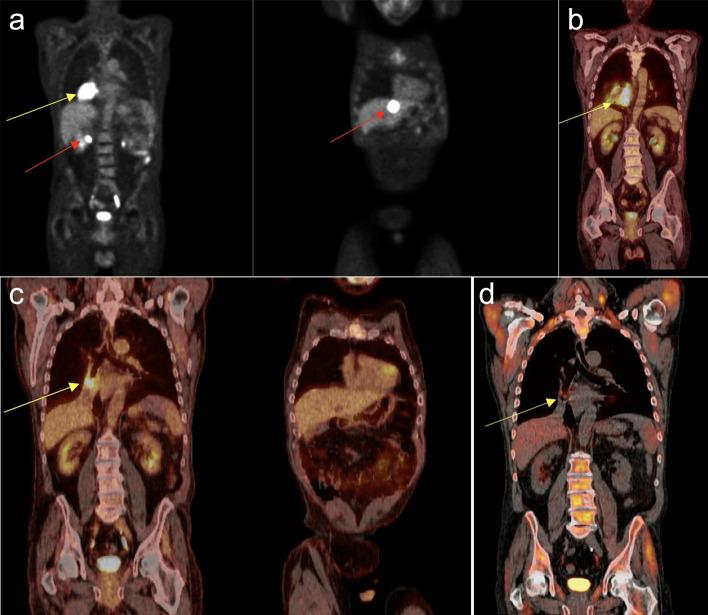

Post-transplant lymphoproliferative disorders (PTLDs) are opportunistic malignancies that complicate the success of hematopoietic stem cell or solid organ transplantation. These disorders often arise post-transplant due to the immunosuppression required for minimizing the risk of rejection of donor tissue. First-line treatment of these disorders includes limiting immunosuppression when permissible. Subsequent treatment includes the use of monoclonal anti-CD20 antibody (rituximab), and/or combination chemotherapy. Chimeric antigen receptor (CAR) T-cell therapy has revolutionized the treatment paradigm in many lymphoid malignancies. It is not approved for PTLD due to exclusion of PTLD patients from pivotal clinical trials. Also, its utilization post-transplant can be complex and multidisciplinary care is of utmost importance for successful administration of a potentially curative treatment. We present a 68-year-old patient with history of heart transplant for non-ischemic cardiomyopathy, diagnosed with PTLD that was refractory to treatment using current guidelines until successfully receiving CAR T-cell therapy.

移植后淋巴细胞增生性疾病(PTLDs)是一种机会性恶性肿瘤,会影响造血干细胞移植或实体器官移植的成功。这些疾病通常在移植后出现,因为需要进行免疫抑制以降低供体组织排斥反应的风险。这些疾病的一线治疗包括在允许的情况下限制免疫抑制。后续治疗包括使用单克隆抗CD20抗体(利妥昔单抗)和/或联合化疗。嵌合抗原受体(CAR)T细胞疗法彻底改变了许多淋巴恶性肿瘤的治疗模式。由于关键临床试验排除了PTLD患者,该疗法未被批准用于PTLD。此外,移植后使用该疗法可能很复杂,多学科护理对于成功实施潜在的治愈性治疗至关重要。我们报告了一名68岁的患者,有非缺血性心肌病心脏移植病史,被诊断为PTLD,按照当前指南治疗无效,直到成功接受CAR T细胞疗法。